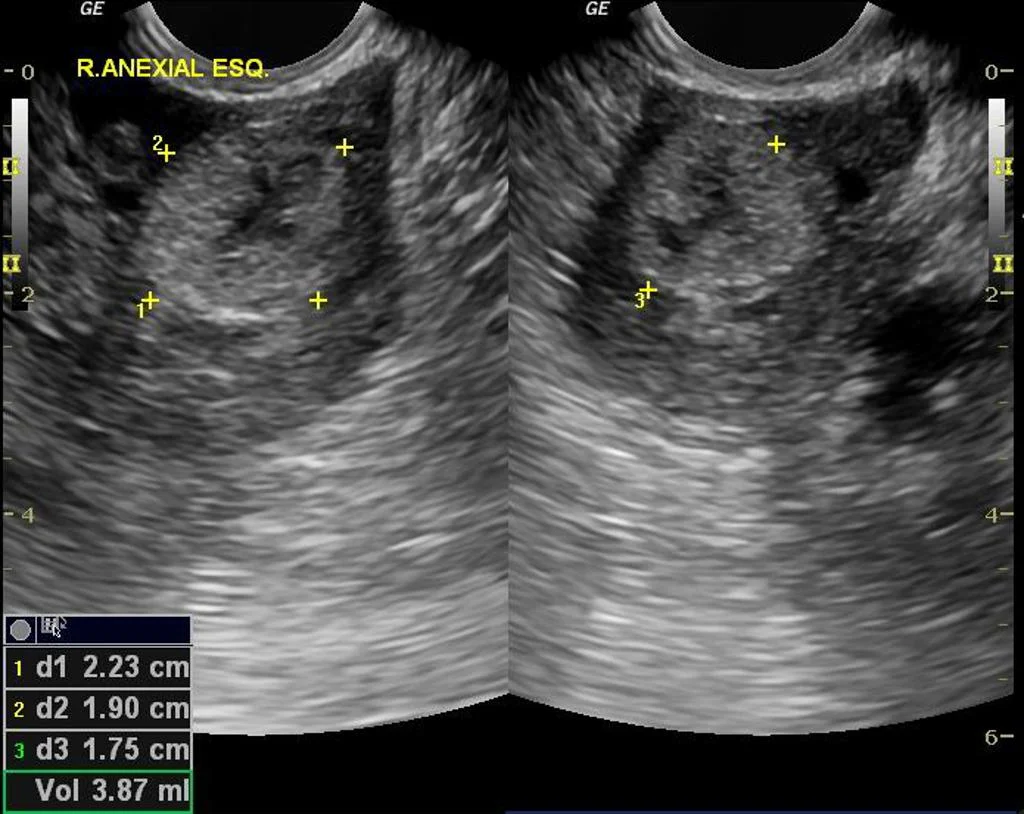

Just as in the trans-abdominal approach, you will be obtaining both long axis (sagittal) views of the uterus and short axis (transverse) views. Sagittal views will be obtained with the probe marker towards the ceiling. Once you identify the uterus in long axis, be sure to pan to the patient's right and left (staying in the same plane) to examine the entire uterus, looking posteriorly and anteriorly for any free fluid. You can then rotate the probe 90 degrees to the patient's right to obtain a short axis view, and scan up and down through the entire uterus from cervix to fundus. You can also identify the ovaries in either long or short axis view (slightly hypoechoic compared to uterus) which will have a "chocolate chip cookie" appearance due to ovarian follicles and are typically found around the body of the uterus, anterior and medial to the internal iliac vessels (though not always).

As you can see above, the majority of ectopic pregnancies will be tubal in location, specifically in the ampulla. Most of these ectopic pregnancies will not able to be directly visualized so you will often be looking for other findings to increase the likelihood of this diagnosis.

• No IUP with concerning dates and abdominal pain or vaginal bleeding

• Ring like adnexal mass with or without the "ring of fire" on color doppler

• Free pelvic fluid

• Live IUP not within the uterus